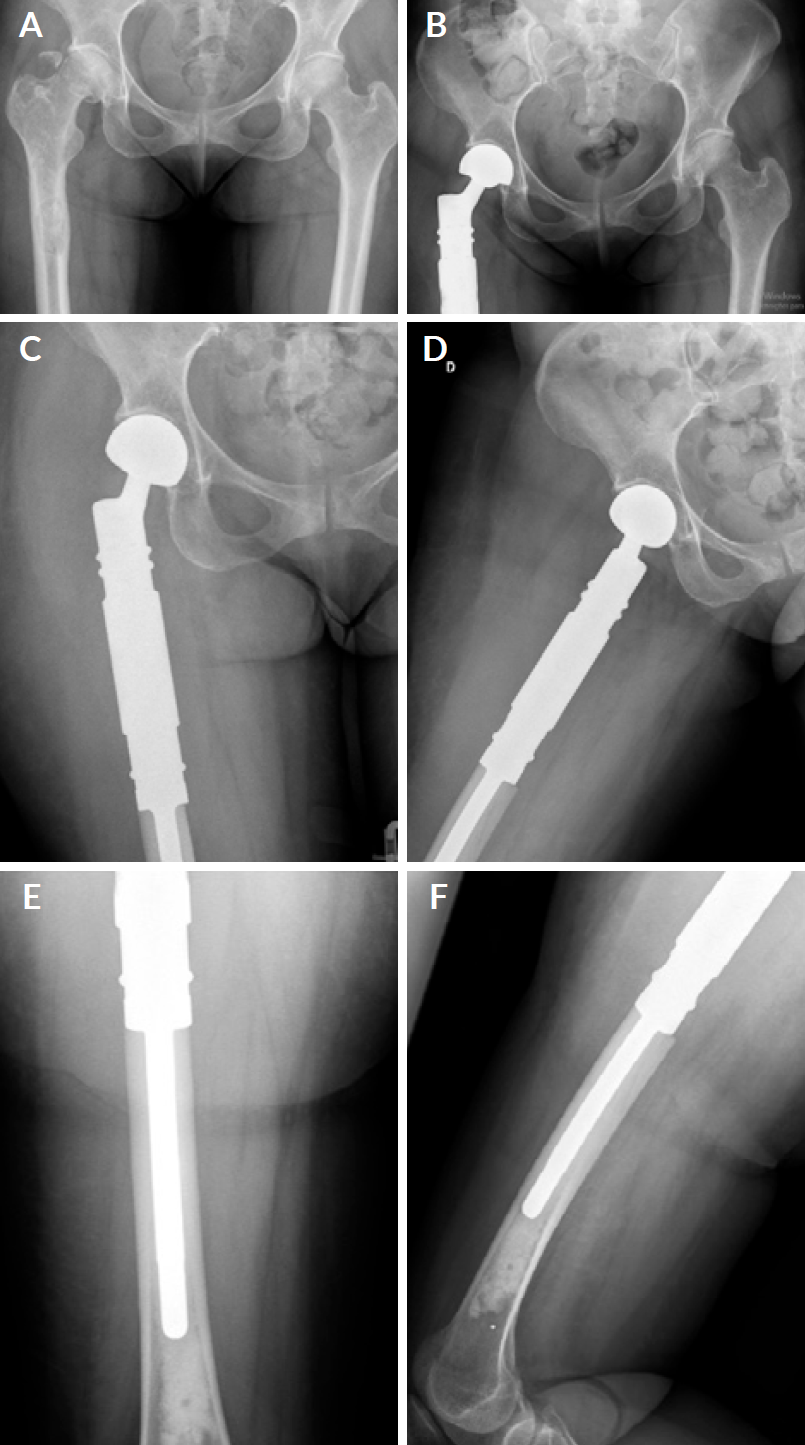

Surgical treatment options included en bloc resection and megaprosthetic reconstruction (Figs. 3A, B, C, D, E and F), osteosynthesis or conventional hemiarthroplasty/total hip arthroplasty. All surgeries were performed by the senior authors. OS was defined as the time from the fracture or impending fracture diagnosis until the date of death. We considered as relevant surgical-related complications those which implicated the need for new surgical procedures. The remaining complications managed without surgical treatment were classified as non-relevant.

Figure 3 3A - Proximal femur pathologic fracture due to lung cancer bone metastasis. 3B, C, D, E and F- En bloc resection and endoprosthetic reconstruction of the right femur.